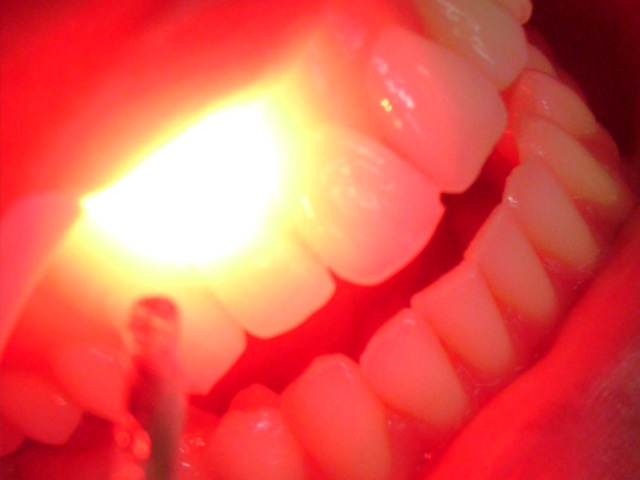

Tratamento com laseres de baixa potência, que agem como bioestimuladores, que elimina a inflamação e acelera o processo de cicatrização e cura. Indicado no pós-cirúrgico, hipersensibilidade dentária, aftas, herpes, nevralgias e outras patologias.

Clique na imagem para ampliar: